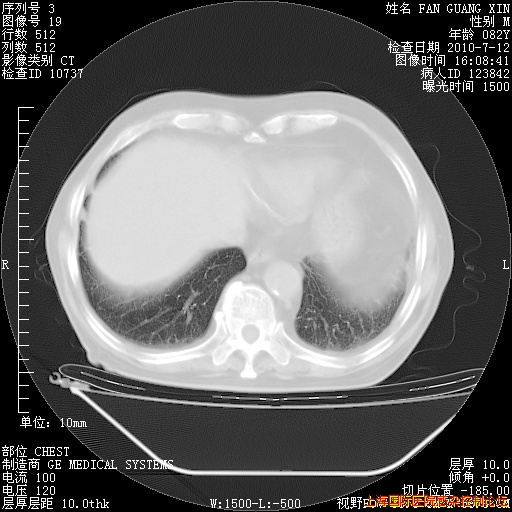

今天复查CT

整整相隔30天的肺部CT好像有所好转啊。甲强龙减量第3天,需要观察体温。